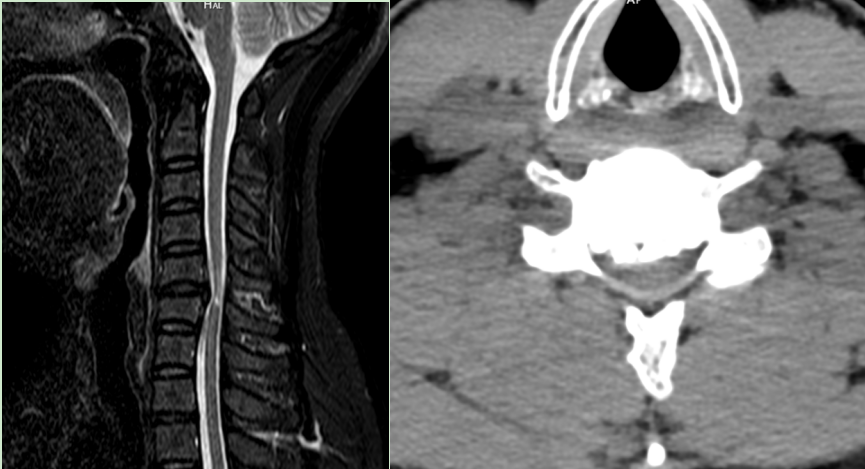

40岁的吴先生(化名),因长期四肢麻木、走路踩棉花感、双手精细动作障碍入院,近一个月症状急剧加重。影像学检查显示:第5、6颈椎间隙重度狭窄,合并椎间盘及后纵韧带重度钙化,脊髓被挤压得“卡到极限”,随时有瘫痪加重的风险。吴先生怀着对瘫痪的恐惧多方求医,最终慕名来到宜昌市中心人民医院。

在3D外视显微镜的全程引导下,肖运祥主任医师、皮闻森医师治疗组完整切除钙化灶、彻底减压脊髓及神经根。术后即刻,吴先生自觉“手脚轻松”,术后第二天肌力明显改善,无脑脊液漏、神经损伤等任何并发症,成功避免了瘫痪的厄运。